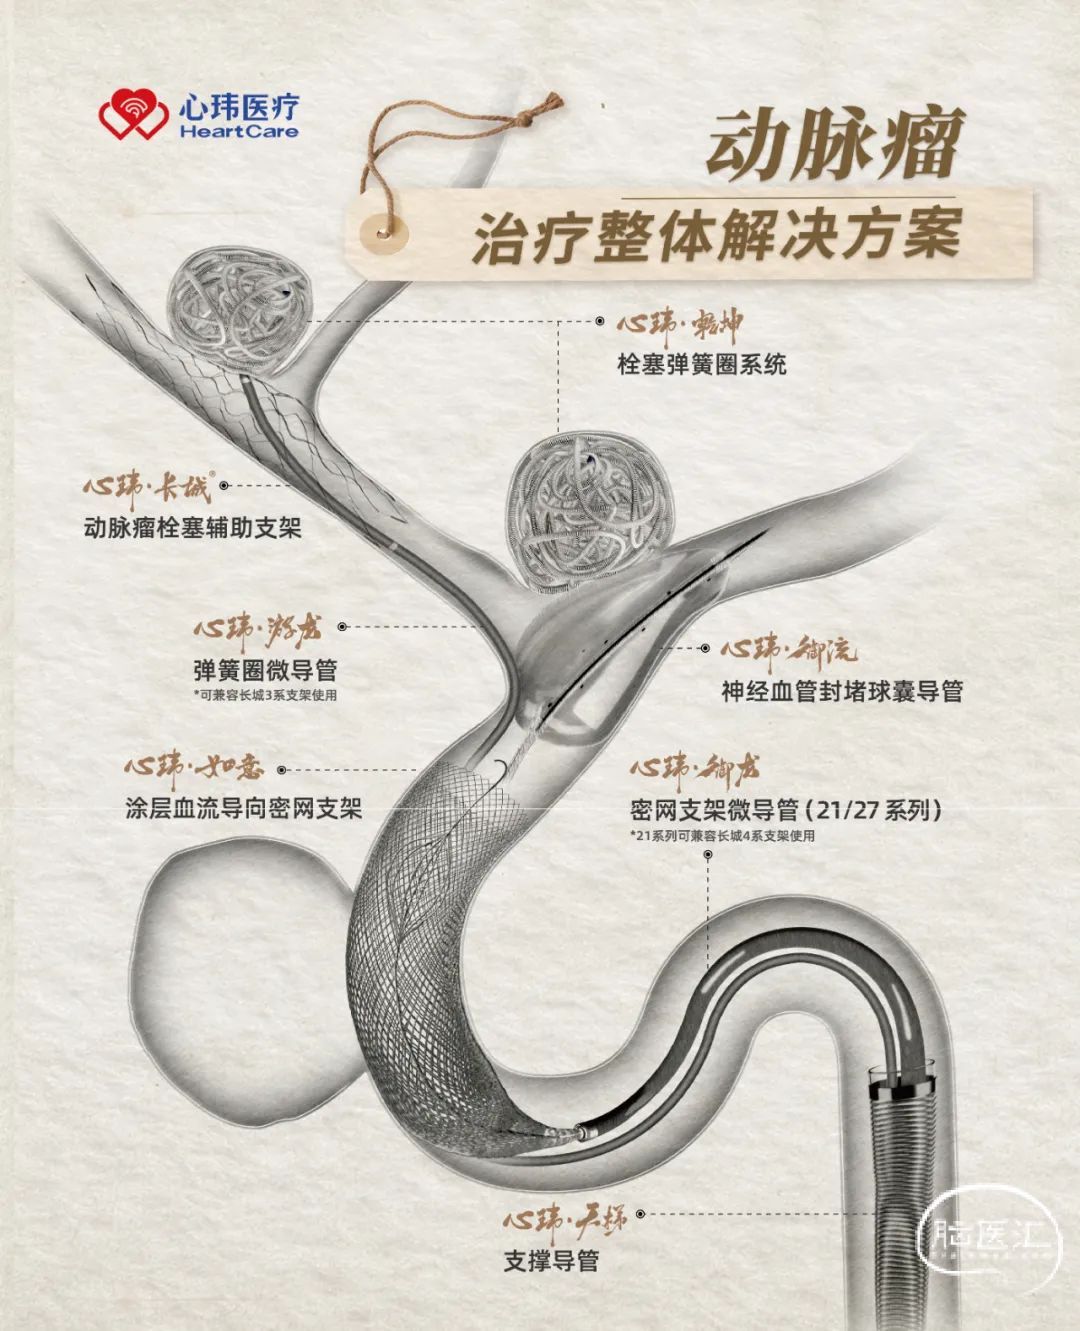

· 需选择较小型号,可通过小系统输送,可自膨打开且径向支撑力足够的血流导向密网支架

· 综上因素,选用心玮“如意”血流导向密网支架进行治疗

手术耗材

· 心玮“如意” FDD-250-20mm 血流导向密网支架

· 心玮DMC 0.021inch 支架微导管

· 6F 115cm 颅内支撑导管

· 8F 90cm 长鞘

· 0.014" 200cm 微导丝

心玮,国产唯一提供动脉瘤治疗整体解决方案商